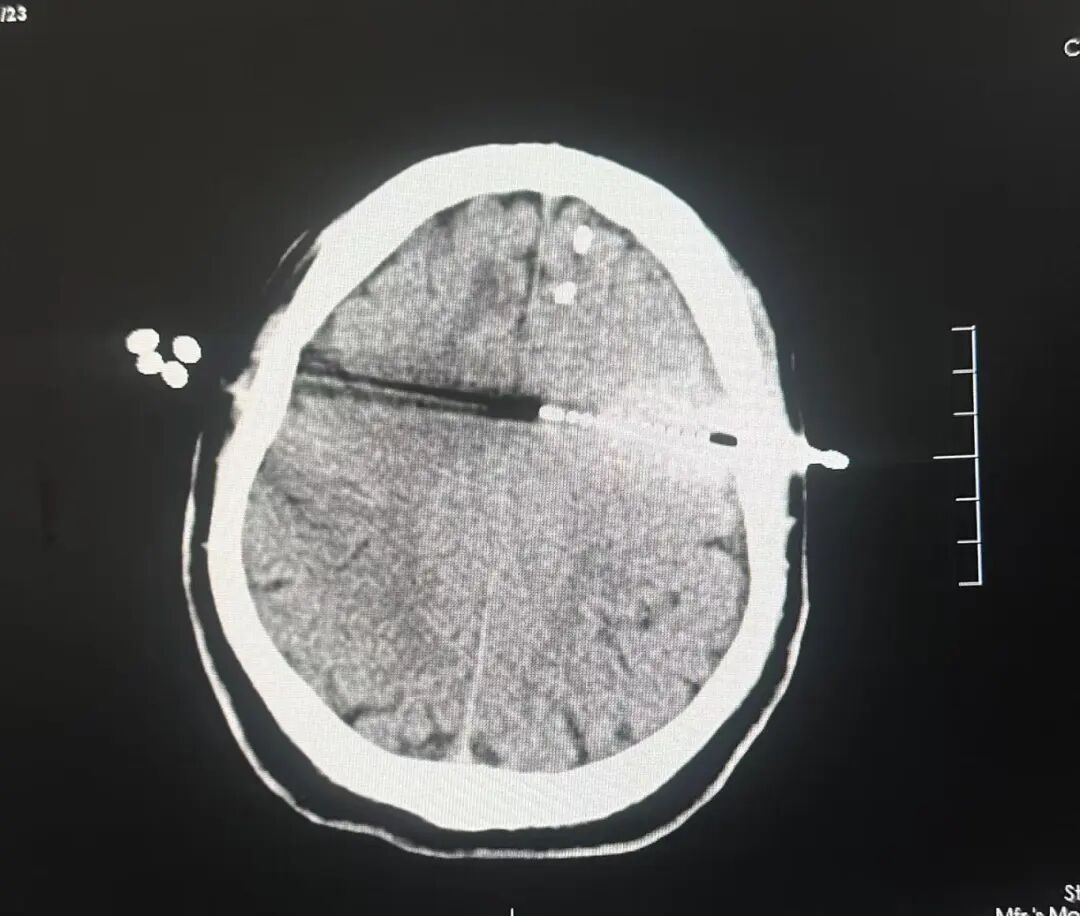

在手术室内,孙康健主任团队在神经外科机器人辅助下为患者植入了多个电极,后在脑电监测下通过检查及电刺激的方式确定了患者的致痫灶位于左侧额叶靠近功能区处,确定位置后为患者进行了二次的立体定向脑电图毁损治疗。现患者恢复良好,手术后癫痫无发作。

机器人辅助植入电极